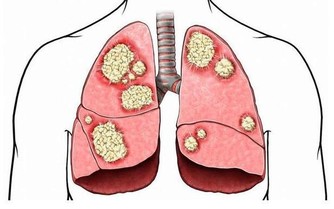

5、婦科腫瘤

如果盆腔內患有腫瘤,如子宮肌瘤、子宮頸癌、卵巢囊腫等,壓迫神經或癌細胞向盆腔結締組織浸潤,均可發生腰痛,並且痛感隨著腫瘤的增大而加劇。